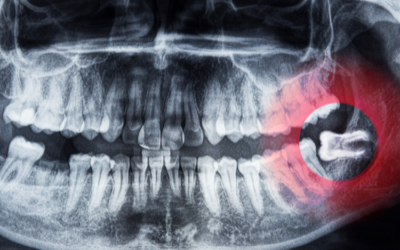

Do All Wisdom Teeth Need to Be Removed? What Dentists Recommend

One of the most common questions patients ask is, “Do all wisdom teeth need to be removed?” The answer depends on your situation. At Emu Plains...

Signs You Might Need Your Wisdom Teeth Removed

Your wisdom teeth are the last set of molars to emerge, typically between the ages of 17 and 25. While some people have no problems with them, for...